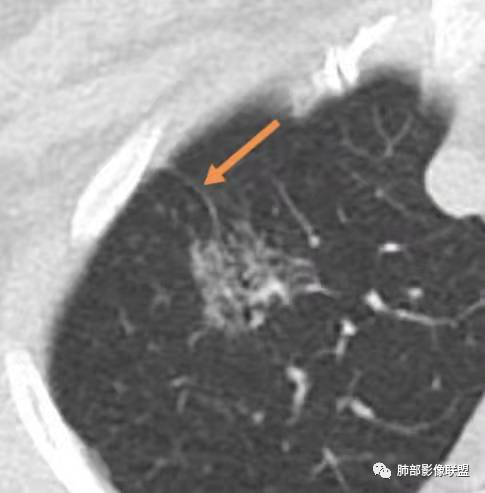

影像特点:右肺上叶混合磨玻璃影,边界清晰,结构松散,内有多结节堆积及支气管扩张影,可见小叶间隔增厚,并局部增厚的小叶间隔上亦存在微结节,胸膜侧可见纤细索条,病灶周围可见多发微结节影。

总体分析:从病灶分布来看符合结核的好发位置,影像表现也符合结核的多态性,且出现卫星灶。由于有边界清晰的GGO,需要鉴别腺癌,虽然此病例有边界清晰的GGO,但是它的GGO的边缘有结节感,呈多结节堆积,而腺癌的GGO缺乏这种“多结节堆积感”,另外,此病例也没有发现腺癌的胸膜凹陷征、毛刺征及月牙铲等。

1、年轻人多见,一般提示免疫力可能有下降。 2、好发部位与其它结核类似,上叶及下叶背段为主。 3、烟花征,反晕征,环呈结节状,可以伴随空洞,树芽征,结节灶,胸水。(反晕征:一般周围实性环形高密度影,中央丛密度低;一般环超过圆的3/4,结核的环主要是小叶核心结节组成,类似于多发树芽征聚集,边缘结节感。中央的晕:可以是腺泡结节,树芽征,细网状,磨玻璃影,很少正常,主要成分是小叶内间质增厚、小叶核心结节、肺泡内病变。)其实也体现了结核的多灶性、多态性特点。

4、其实不一定完全表现为反晕征,还有比较密集的烟花,聚集成团,与反晕征同在。